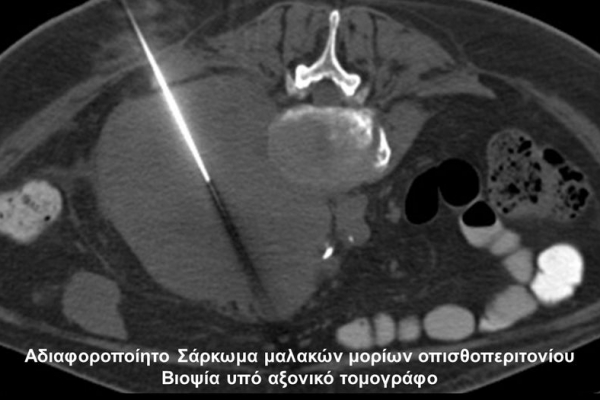

Η οστική βιοψία και η βιοψία όγκων μαλακών μορίων χρησιμοποιείται για την ιστολογική διάγνωση αλλοιώσεων (καλοήθων - κακοήθων / πρωτοπαθών ή μεταστατικών) ή για τη λήψη υλικού προς καλλιέργεια ώστε να αναδειχθεί το μικρόβιο που προκαλεί τη λοίμωξη του μυοσκελετικού συστηματος (πχ σπονδυλοδισκίτιδα). Η βιοψία υπό συνεχή απεικονιστική καθοδήγηση συμβάλλει στην υψηλή ακρίβεια τοποθέτησης της βελόνης εντός της βλάβης με ασφαλή προσπέλαση. Η χρήση σύγχρονων ομοαξονικών συστημάτων βιοψίας (coaxialtechnique) επιτρέπει την λήψη πολλαπλών δειγμάτων με μια μόνο παρακέντηση.